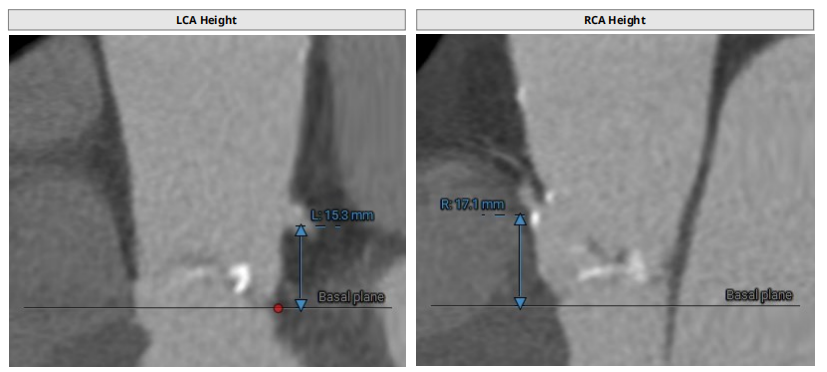

主动脉根部:

三叶瓣,轻度钙化,法式窦结构尚可,左冠开口高度约15.3mm,右冠开口高度约17.1mm,STJ高度约22.6mm、直径约28.8mm,升主动脉未见明显扩张,心脏角度约42°,左室形态大小可,左冠切线位:LAO40° CRA9°,右窦居中位:LAO34° CRA3°,左右重叠位:LOA4° CAU23°。